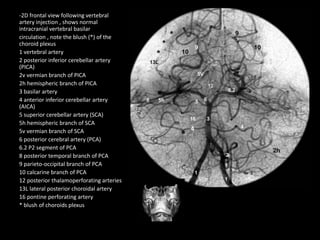

-2D frontal view following vertebral

artery injection , shows normal

intracranial vertebral basilar

circulation , note the blush (*) of the

choroid plexus

1 vertebral artery

2 posterior inferior cerebellar artery

(PICA)

2v vermian branch of PICA

2h hemispheric branch of PICA

3 basilar artery

4 anterior inferior cerebellar artery

(AICA)

5 superior cerebellar artery (SCA)

5h hemispheric branch of SCA

5v vermian branch of SCA

6 posterior cerebral artery (PCA)

6.2 P2 segment of PCA

8 posterior temporal branch of PCA

9 parieto-occipital branch of PCA

10 calcarine branch of PCA

12 posterior thalamoperforating arteries

13L lateral posterior choroidal artery

16 pontine perforating artery

* blush of choroids plexus